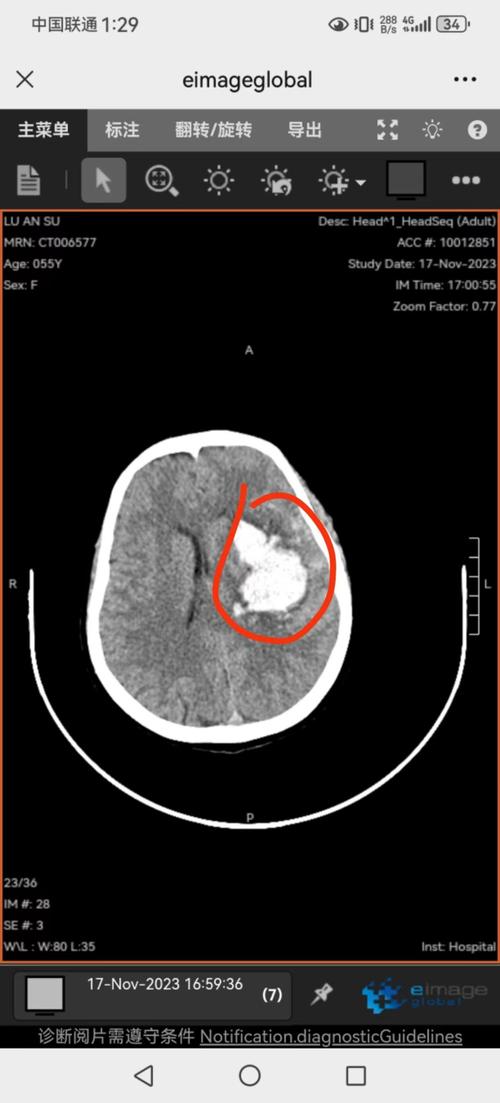

如何诊断?

诊断新生儿侧脑室出血的“金标准”是头颅影像学检查,对于新生儿,首选床旁头颅超声。

- 头颅超声: 这是一种无创、无辐射、可以在宝宝保温箱旁进行的检查,通过宝宝未闭合的囟门,可以非常清晰地观察到脑室内的结构和出血情况,是筛查和随访的首选。

- 头颅CT: 当怀疑有IV级出血或需要更清晰地观察骨骼结构时,医生可能会建议做CT,CT能更快速地显示出血的范围和是否伴有脑实质损伤,但有一定辐射。

- 头颅MRI: 对于评估脑损伤的长期预后,MRI是最佳选择,可以更清晰地显示脑白质和神经纤维的损伤情况,但检查时间较长,对宝宝状态要求较高,通常在病情稳定后进行。